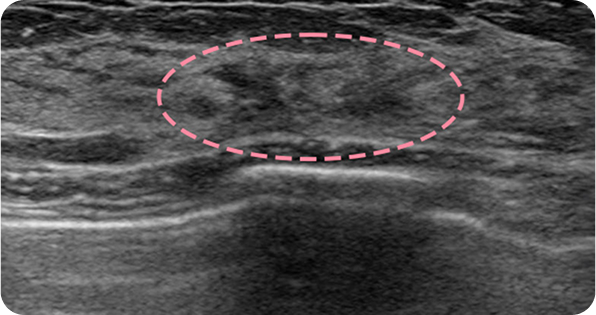

양성 종양은 여러 개가 동시에 생겨나기도 합니다. 정상적인 유방 조직 보전에 신경 쓰며 맘모톰 시술을 섬세히 진행했고, 6개월 뒤 추적 관찰을 위한 유방초음파에서 종양이 깨끗이 제거된 것을 확인했습니다. 일부 반흔 조직은 자연스럽게 호전될 것으로 보여 좋은 예후가 기대되었습니다.